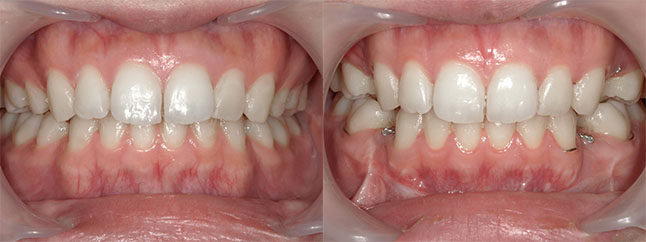

大阪府 22歳 女性

執刀医 辻和志

【治療内容】上のアゴと下のアゴの両方にこんもり感があったため、上下のアゴの骨をきって後ろに下げました。

【費用】上下セットバック 2,307,800円(税込)

【リスク】全身麻酔で行うため全身の健康状態が悪い方は行うことができません。また、手術当日は安静にしていただく必要があります。